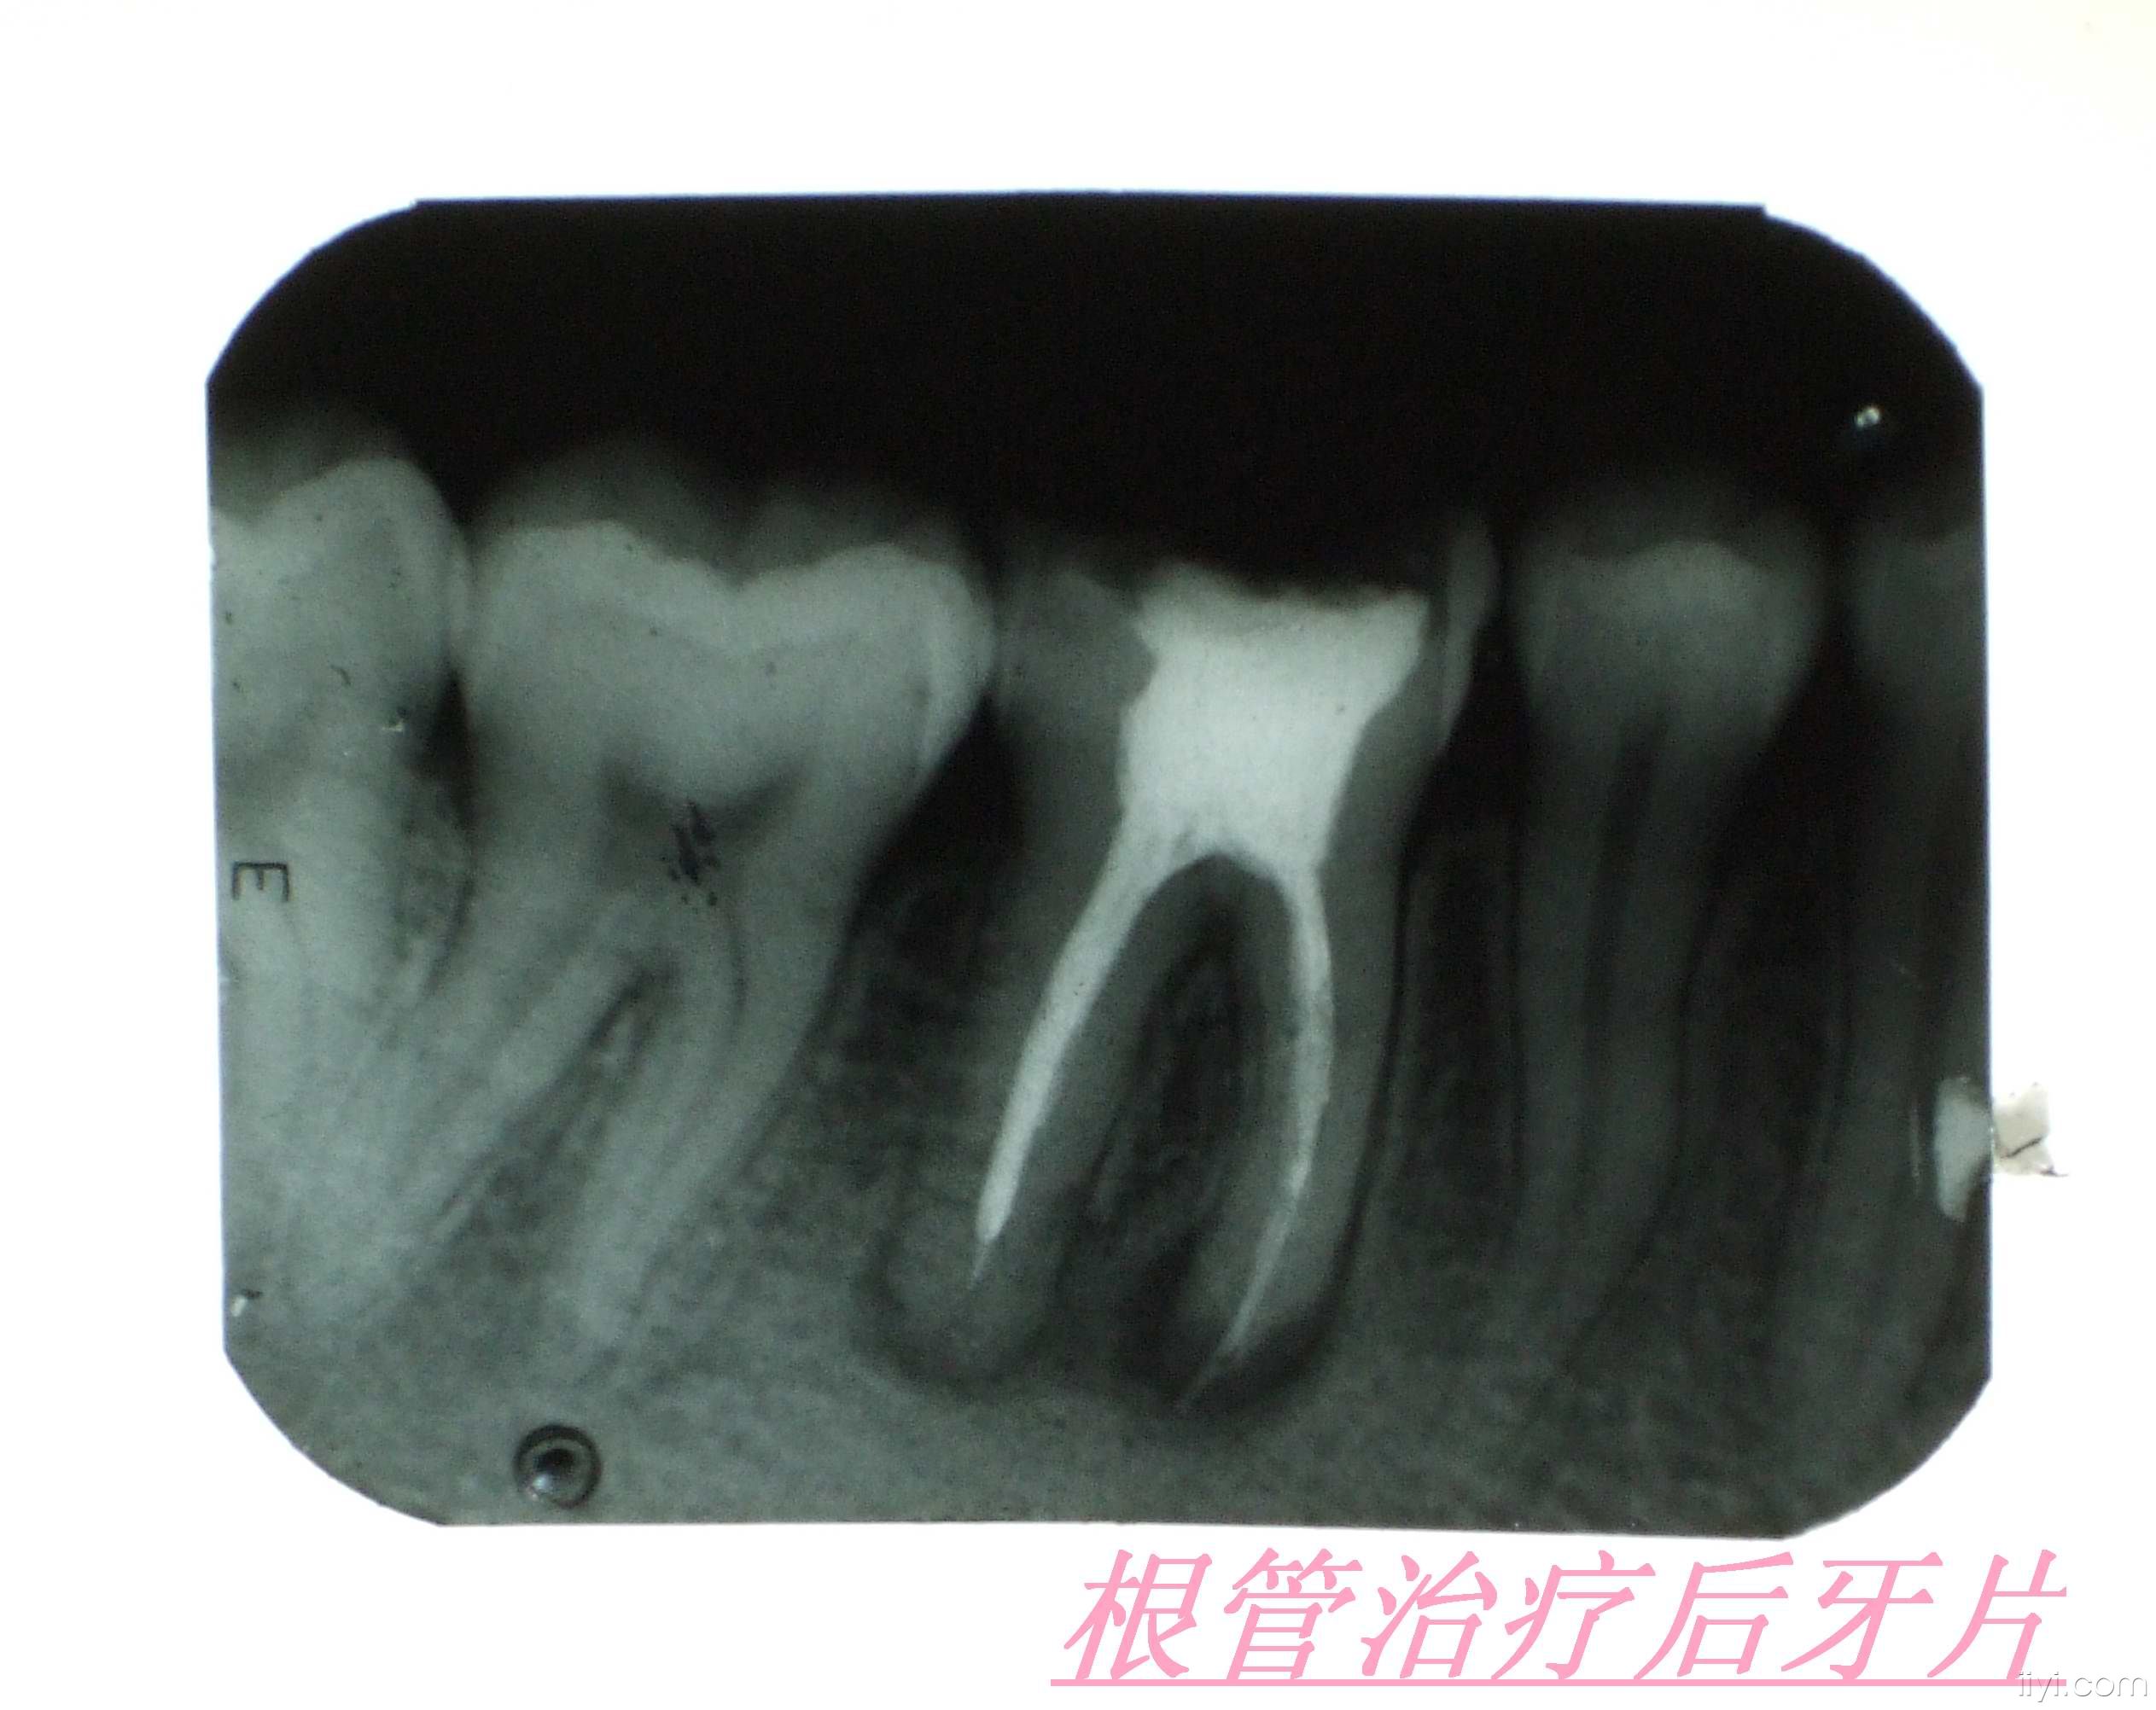

1、一般根管治疗后都是建议要套一个冠。根管治疗后套冠是为了保护失去活力的牙齿,防止牙齿崩裂。

3、定期口腔检查,每半年或者一年检查根管后牙齿的情况,根管后根尖的状况。